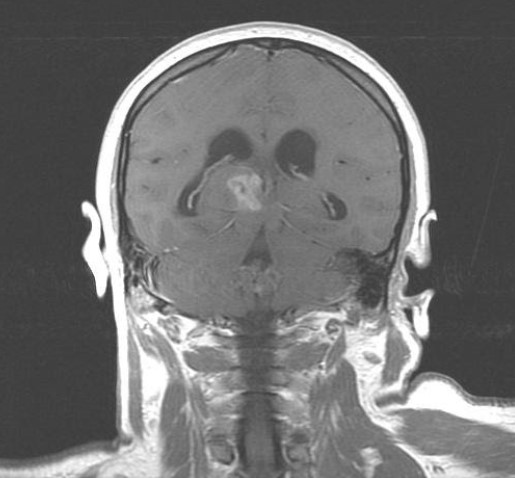

Опухоли после мрт

Опухоли после мрт 113 фото